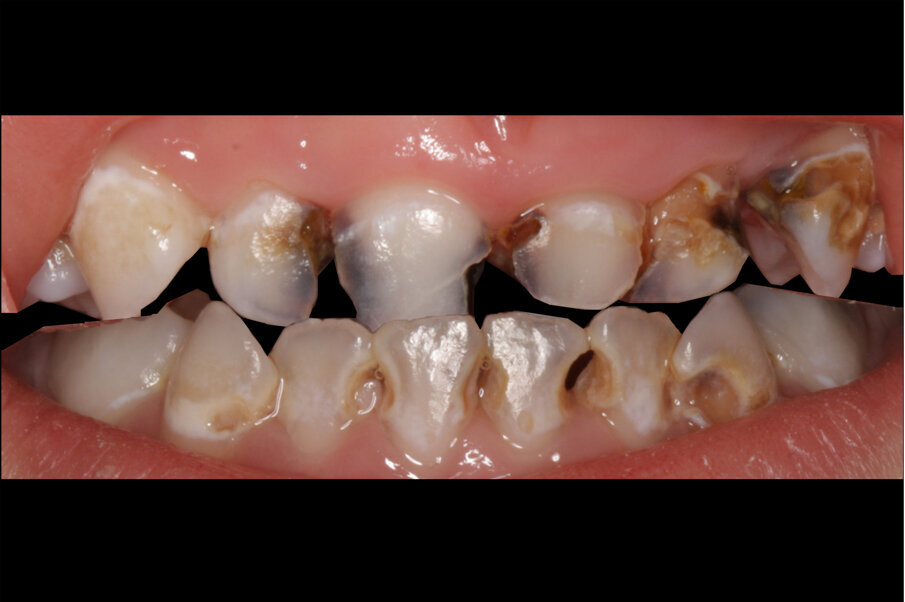

Afbeelding 3. Casus 2: 29-09-17. Eerste bezoek. Actieve cariës-instructies en ZDF aangebracht.

Afbeelding 4. Casus 2: 09-02-18. Tweede bezoek. Na 4 maanden klachtenvrij.